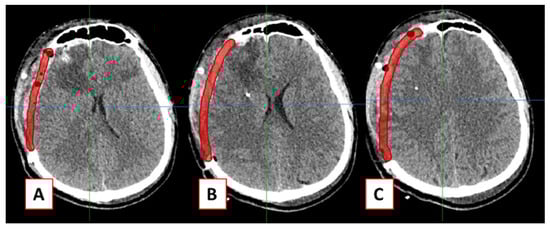

2.1. Design of Cranial Implants Using 3-Matic Software

2.2. Design of Cranial Implants Using MITK Software